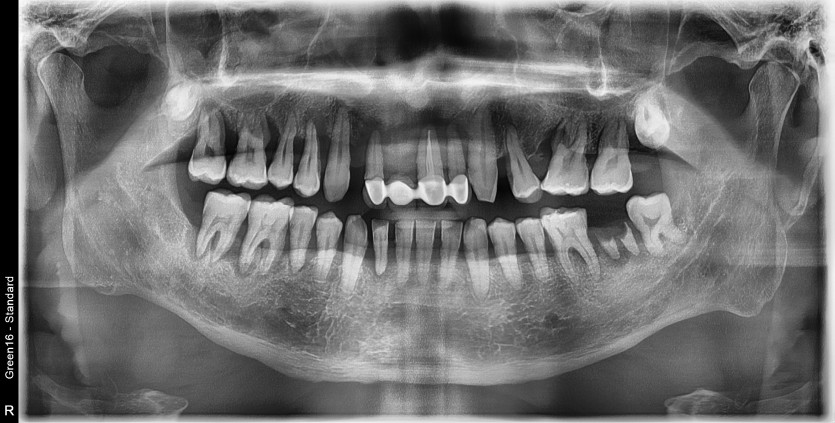

만 40세 상악 전체 임플란트 증례(하악 일부)

상악 전체 임플란트 증례입니다.(하악 일부)

14개의 임플란트로 완성하였습니다.